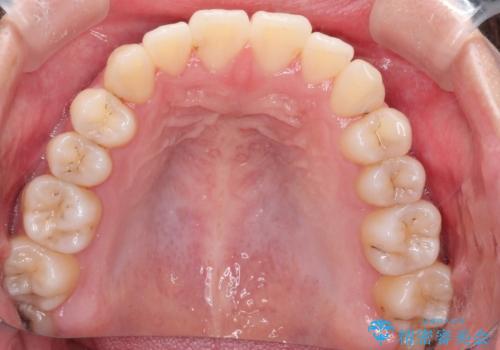

インビザラインによる非抜歯矯正 ガタガタな歯並びを整った歯並びへ

- 前歯のガタガタを主訴に来院されました。

抜歯矯正も考えられる状態でしたが、非抜歯矯正を希望されました。

使用時間を守っていただけたので、スムーズに治療を終わることができました。